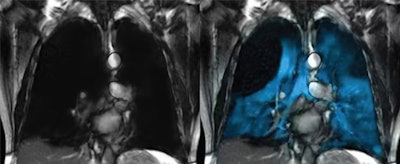

Xenoview. Image courtesy of Philips.

The emerging technique uses hyperpolarized xenon gas as a signaling agent, which allows clinicians to see how air flows through different parts of the lungs in real time. Xenon MRI is approved in the U.S. for evaluating lung ventilation in adults and children ages 12 and older and is now pending approval for children as young as 6, Philips noted.

The technology is comprised of Polarean’s Xenoview 3-tesla chest coil, which is integrated into Philips' clinical workflow across 3-tesla MRI systems. The scan requires just two 10-second breath holds and can be completed in under a minute, the company added.